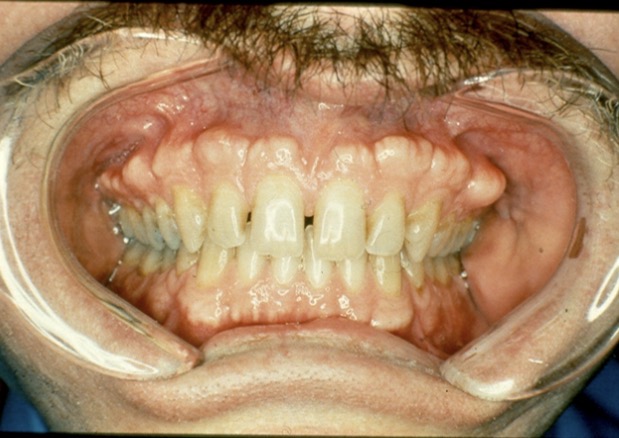

Condition?

Drug induced gingival enlargement

What drugs can cause gingival enlargement?

cyclosporine (SandimmuneĀ®)

dilitiazem (CardizemĀ®)

nifedipine (Procardia)

diphenylhydantoin (DilantinĀ®)